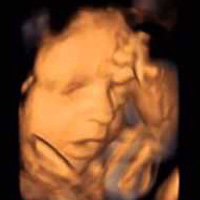

Rebecca Oldham và con trai James. Rebecca Oldham và con trai James. Ảnh: Mirror